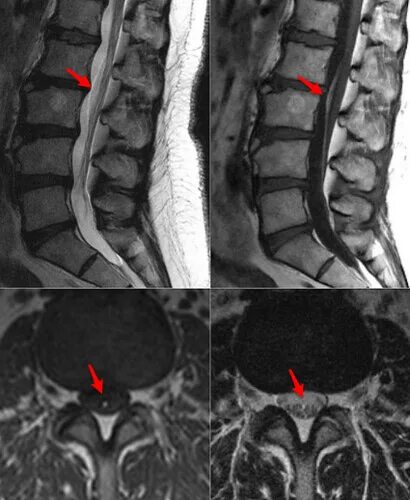

Limbus 3